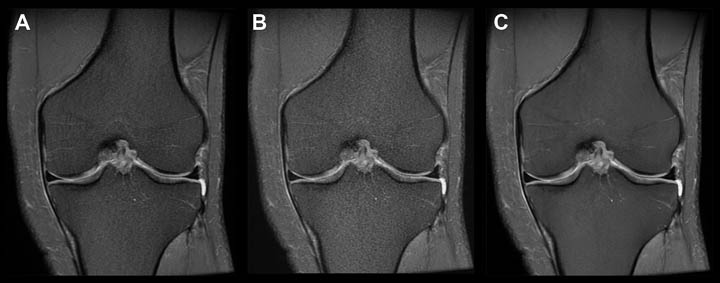

- Knee MRI current image quality, this sequence takes a little over 2 minutes to perform.

- Image quality is visibly degraded when the protocol is adjusted to decrease scan time to 1 minute using conventional methods.

- Image quality is sharper and less noisy when scan time is decreased to 1 minute and the images are reconstructed using the machine learning algorithm.

Data collected at Shields Framingham in collaboration with GE Healthcare.